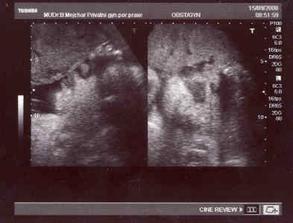

29.2- další velké nervy, čekání na srdíčko - na UTZ byla vidět krásná srdeční akce, Zdenda byl se mnou v ordinaci a měli jsme obrovskou radost!!!...jsme nyní na začátku 8.tt (7+0) - to je ještě dlouhá cesta....

12.3. - první prohlídka v poradně a už jsme dostali těhotenskou průkazku!!! máme další fotečku, kde už miminko vypadá opravdu jako človíček 🙂)

2.4. - podrobný UTZ (screaning v I.trimestru a vše v pořádku hurááá) - mimčo je čiperné, krásně na UTZ skotačí!!!